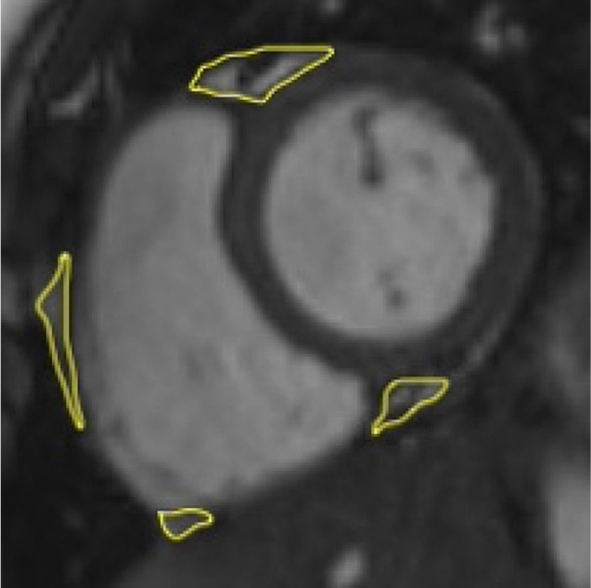

Background: Epicardial adipose tissue (EAT) is a biologically active visceral brown adipose tissue, which is irregularly distributed across myocardium. It has emerged as a potential modifiable cardiometabolic biomarker in adults, demonstrating pro-inflammatory properties with involvement in subclinical atherosclerosis. The increased thickness of the inner two layers of the carotid artery wall (intima and media) in childhood can pose as a risk of the development of atherosclerotic disease and its complications in adult life, representing additional potential biomarker. The purpose of our study was to evaluate a relation between EAT volume (EATV) and carotid intima-media thickness (cIMT) in children and adolescents who have been diagnosed with primary arterial hypertension (AH), utilizing magnetic resonance imaging (MRI).

Patients and methods: The study included 72 children and adolescents, half of them had an established diagnosis of primary AH and the other half were matched healthy controls. The EATV and cIMT measurements were compared between the two groups and correlated with clinical, anthropometric and functional parameters.

Results: Children diagnosed with AH exhibited a significantly higher EATV (16.5 ± 1.9 cm3 vs. 10.9 ± 1.5 cm3; t = -13.815, p < 0.001) and higher cIMT (0.7 [0.2] mm vs. (0.4 [0.1) mm]; U = 54, p < 0.001) compared with their healthy counterparts. EATV demonstrated a significant correlation with cIMT.

Conclusions: Increased EATV and cIMT were found with MRI in hypertensive children compared to their healthy counterparts. EATV demonstrated a stronger association with hypertension than cIMT. EATV emerged as an independent predictor of cIMT.